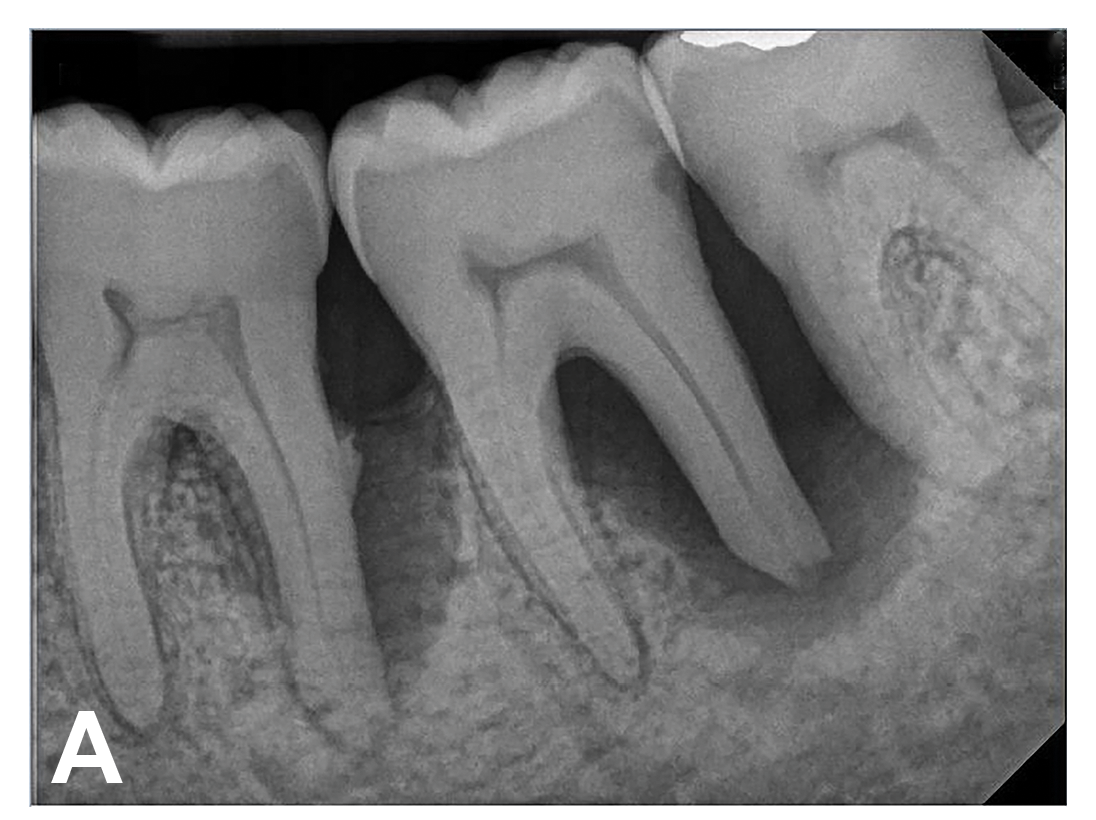

A 63-year-old male patient with a medical history of asthma, hay fever, sinusitis, and arthritis was referred for periodontal therapy in November 2015. He reported taking multivitamins, fish oil, and naproxen sodium occasionally for pain. The patient did not report experiencing any dental discomfort. The clinical findings, radiographic interpretations, diagnosis, and preoperative prognosis for teeth Nos. 17 through 19 are summarized in Figure 6 and Table 1. The patient was informed that teeth Nos. 17 and 18 should be extracted and that tooth No. 19 would need regenerative therapy. A treatment plan was devised for phase I and phase III periodontal therapy, and the patient consented to the proposed treatment verbally and in writing.

(6.) Initial periapical radiograph taken on November 15, 2015, showing infrabony defect approaching the apex of the distal root of tooth No. 19, on which there was a calcified mass (hypercementosis) and evidence of furcal bone loss. The entire distal root of tooth No. 18 appeared to have no bone support, and a small arrested carious lesion was noted on the distal crown of tooth No. 18. Teeth Nos. 17 and 18 were initially given a hopeless prognosis and slated for extraction.

Figure 6